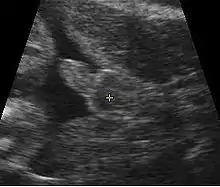

Obstetric ultrasonography, either transvaginally or transabdominally, checks for various markers of fetal sex. It can be performed at or after week 12 of pregnancy. At this point, 3⁄4 of fetal sexes can be correctly determined, according to a 2001 study.[53] Accuracy for males is approximately 50% and for females almost 100%. When performed after week 13 of pregnancy, ultrasonography gives an accurate result in almost 100% of cases.[53]

Prenatal sex determination is restricted in many countries, and so is the communication of the sex of the fetus to the pregnant woman or her family, in order to prevent sex selective abortion. In India, prenatal sex determination is regulated under the Pre-conception and Prenatal Diagnostic Techniques (Prohibition of Sex Selection) Act 1994.[55]

- Availability

China launched its first ultrasonography machine in 1979.[13] Chinese health care clinics began introducing ultrasound technologies that could be used to determine prenatal sex in 1982. By 1991, Chinese companies were producing 5,000 ultrasonography machines per year. Almost every rural and urban hospital and family planning clinics in China had a good quality sex discernment equipment by 2001.[56]

The launch of ultrasonography technology in India too occurred in 1979, but its expansion was slower than China. Ultrasound sex discernment technologies were first introduced in major cities of India in the 1980s, its use expanded in India's urban regions in the 1990s, and became widespread in the 2000s.[57]

Traditional Chinese techniques have been used to determine sex for hundreds of years, primarily with unknown accuracy. It was not until ultrasonography became widely available in urban and rural China that sex was able to be determined scientifically. In 1986, the Ministry of Health posted the Notice on Forbidding Prenatal Sex Determination, but it was not widely followed.[69] Three years later, the Ministry of Health outlawed the use of sex determination techniques, except for in diagnosing hereditary diseases.[70] Individuals or clinics that violated the ban on prenatal determination at the request of the mother were subject to financial penalties, and the ban was repeatedly affirmed in the 1980s, early 1990s, and early 2000s.[71] However, many people have personal connections to medical practitioners and strong son preference still dominates culture, leading to the widespread use of sex determination techniques.[13]

Rutherford and Roy, in their 2003 paper, suggest that techniques for determining sex prenatally that were pioneered in the 1970s, gained popularity in India.[91] These techniques, claim Rutherford and Roy, became broadly available in 17 of 29 Indian states by the early 2000s. Such prenatal sex determination techniques, claim Sudha and Rajan in a 1999 report, where available, favored male births.[92]